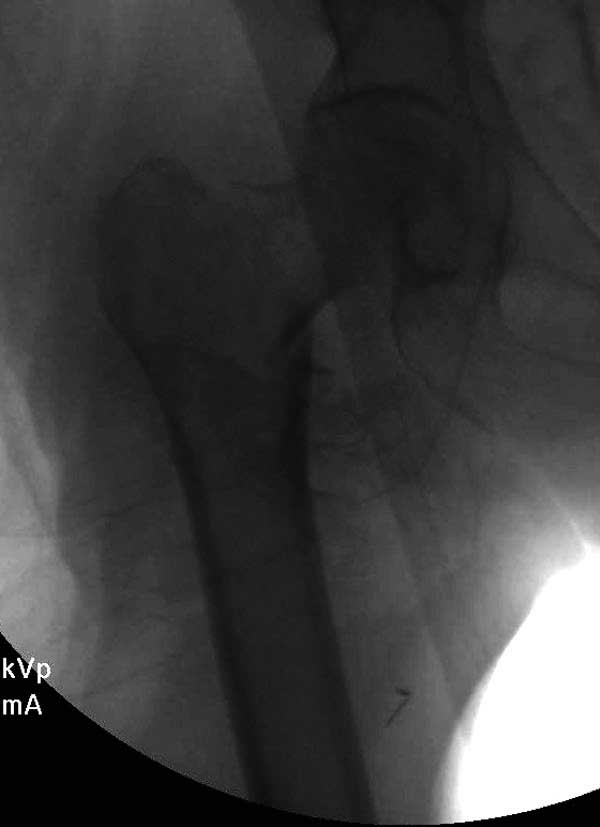

Сеньоры-пэры ревизировали гвоздем, шуруп поставили по той же дорожке, только поглубже. Да еще и bone graft не пожалели. "Результат" уже был через 2 дня.

No comment.

End of story.

Неужели фиксация протеза бесцементная? Да и чашка не запрессована как надо.Грустно(

Эт -ж биполяр:)) Ножка цементная. Страйкеровский Exeter.1

биполярный эндопротез все же не лучший выбор для данной ситуации.судя по снимкам мышечные прикрепления на вертелах утрачены.Возможно здесь подошла бы более стабильная конструкция.Ваше мнение?

а куда делся фрагмент большого вертела? Очевидно,

Если среднеягодичная мышца не рефиксирована, то ничто не держит протез во впадине и это закономерный результат.

Третья операция-продолжения усилии “синьорами пэрами” по разрушению нормальной анатомии. Крест на головку! По видимому возраст позволяет биполярную конструкции, и при дефекте calcar пошли на обычный цементный. Ягодичные мышцы потеряли связь с вертелом, т.е. отсутствует верхний удержатель, и результат “a Big Screw Up!” Снимки вызывают головокружение!

Если хирурги не устали от своих “творчеств”, тогда можно ре-оперировать с calcar replacement stem, и собрать остаток ягодичных мышц. Глубина и отстутствие артроза позволяет применить любой, биполярный или тотальный, хотя принять решение можно после ревизии ацетабулума.